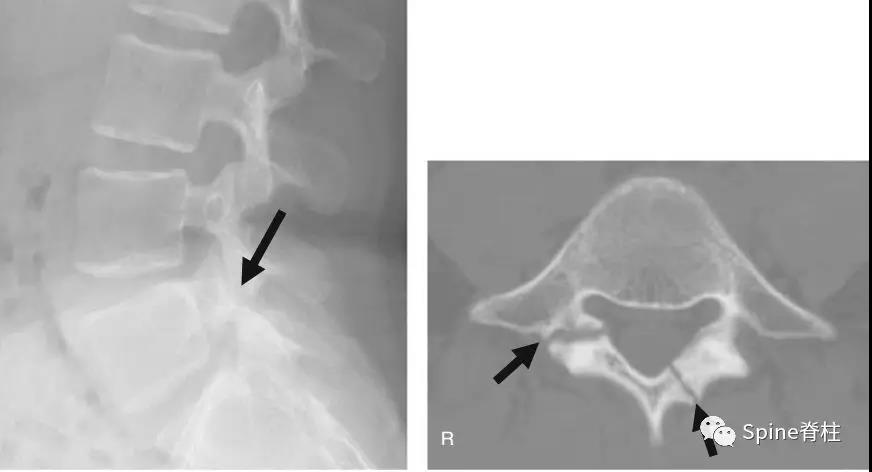

2003年发表在Am J Sports Med杂志(IF=6.20)上的病例报道,很好的阐述了峡部裂和椎弓根裂的变化。描述一个17岁的棒球运动员,运动后腰痛1月余,随访的辅助检查提示相同椎体水平出现的3个连续性应力性骨折:第一次为左侧峡部,第二次为右侧椎弓根,第三次为右侧峡部。

图:起始CT提示L5左侧峡部裂(双箭头),起始CT检查后2个月复查可见出现右侧椎弓根裂(单箭头),4个月复查可见椎弓根裂愈合(单箭头)